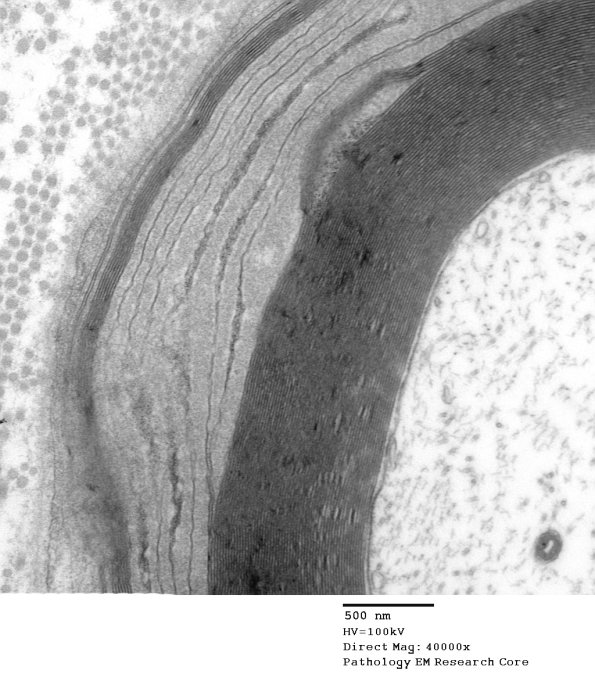

In some cases the lamellae are extensively tangential and may obscure the nature of the process. (electron micrograph)